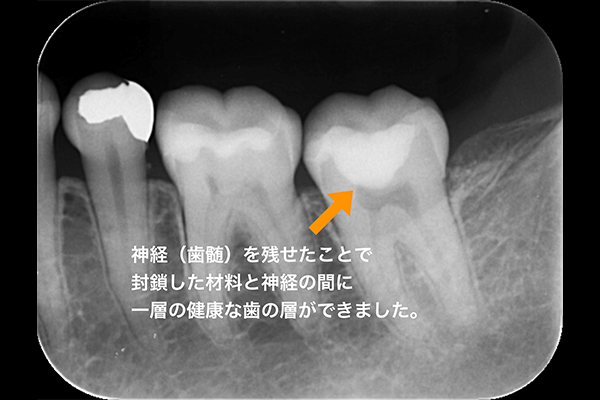

7.治療後のレントゲン

術後3年半経過のレントゲン写真です。

残した神経と、MTAの間に一層の健康な歯の層が出てきていることが確認できます。

神経が治る力を発揮してくれている事がわかります。